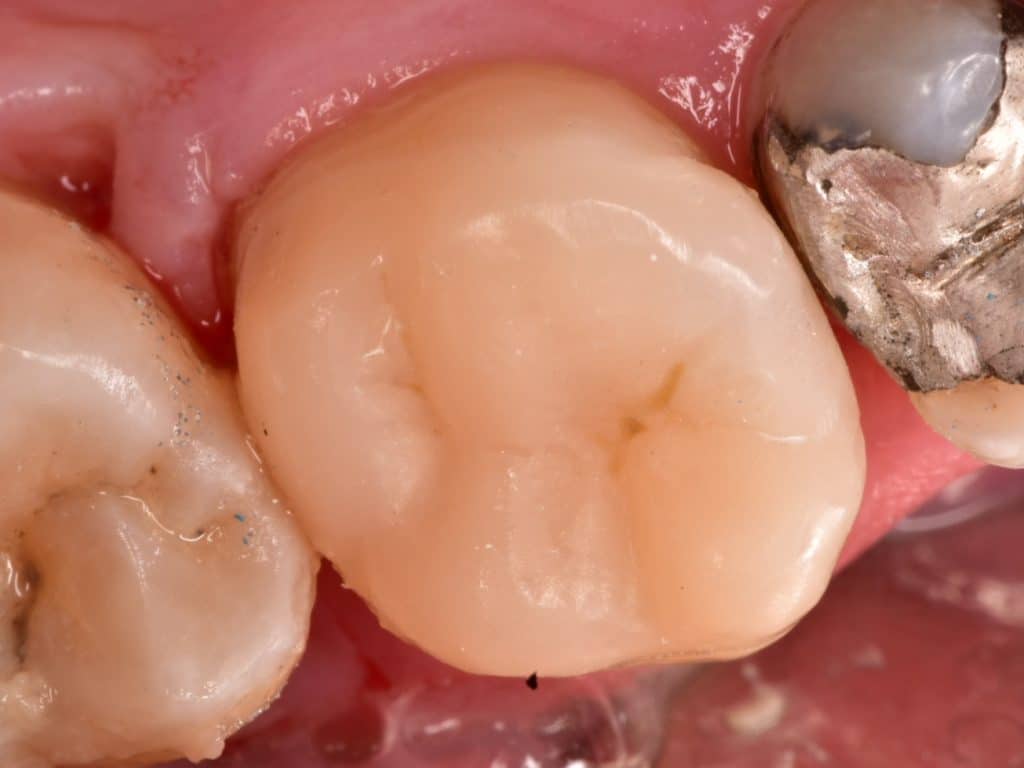

After rubber dam removal

Final result,